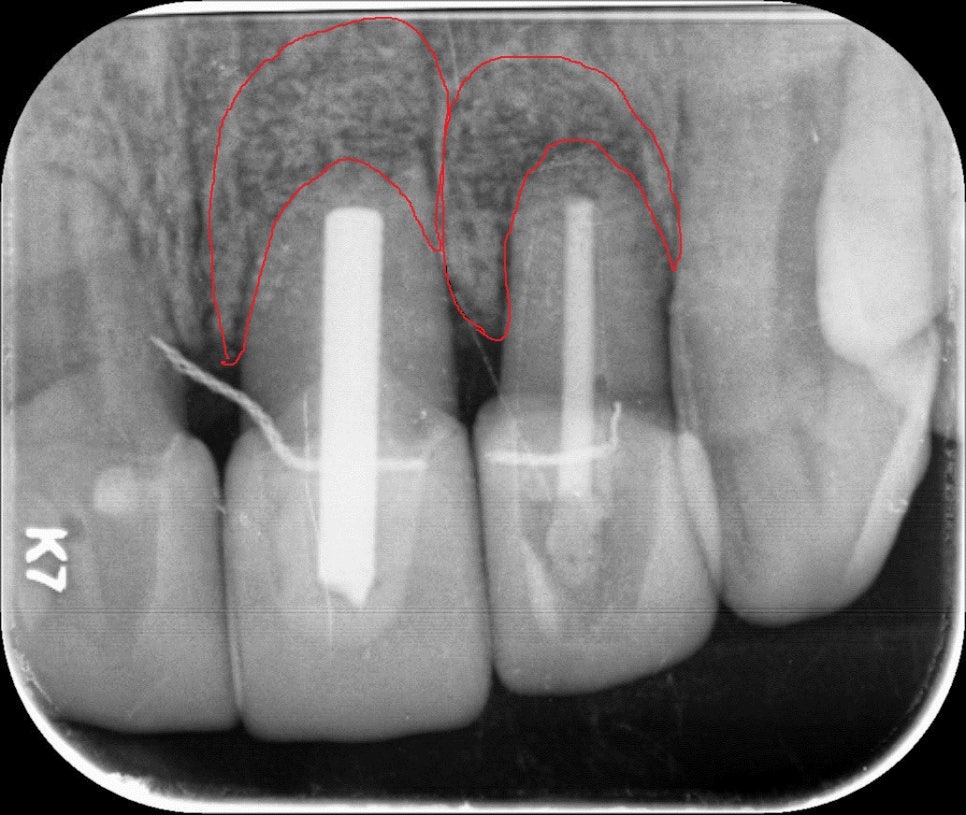

앞니 쪽에 지속적으로 통증이 있어 진단 후 치근단절제술을 시행하기로 하신 케이스로, 뿌리 조직의 염증을 제거 후 부족한 치조골(잇몸뼈)에 뼈이식으로 함께 진행합니다.

치아뿌리염증 _치근단절제술

치근단 절제술 후 뼈이식

치근단절제술 하긴 전 병변 사진 (붉은색으로 표시)

(위 그림) 붉은색으로 표시된 부위의 치아 뿌리 부분의 염증조직 (아래 그림) 치근단 절제술로 제거 후 뼈이식술 함께 진행된 방사선 사진

(왼쪽) 치아 뿌리 병변 조직 확대 / (오른쪽) 치근단 절제술 + 뼈이식 후 x-ray